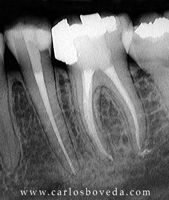

Video de un Retratamiento de Conductos en Una Sesión - (formato Quicktime)